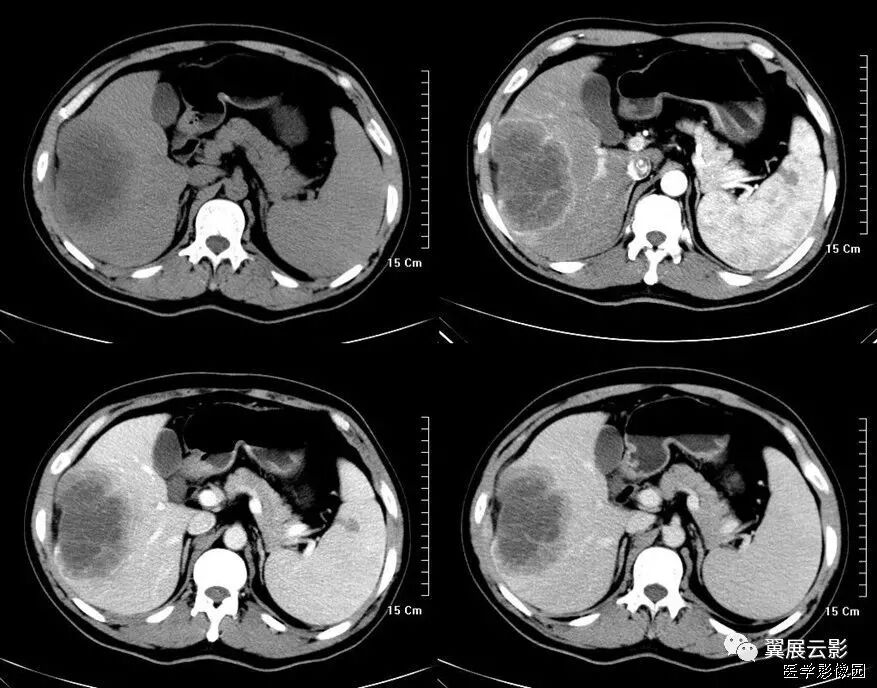

25、肝包膜凹陷征(肝包膜退缩征)

腹部CT扫描时,位于肝脏表面的恶性肿瘤,肝包膜内陷,失去原有的弧度,并与其相续的肝包膜构成一个完整的大弧度,谓之肝包膜凹陷征。

肝恶性肿瘤的发展过程中,小血管,小胆管阻塞引起局限性肝萎缩,肿瘤中央坏死、瘤周纤维组织增生并侵犯肝包膜等多种因素,致使肝包膜向肝内方向收缩,共同导致包膜凹陷征。

虽然肝包膜凹陷征在肝脏恶性肿瘤中出现率并不高,但邻近肝脏肿块的肝包膜凹陷征在许多种恶性肿瘤中都可以出现,包括肝细胞性肝癌、纤维板层性肝、肝内胆管细胞癌、肝转移瘸(原发肿增多为结肠癌、乳腺癌、类癌、肺癌、胆囊癌、胃癌、胰腺癌等)。其病理基础是瘤体中心由于代谢旺盛,血供相对不足,易发生坏死囊变,邻近肝表面的病灶坏死后埸陷,牵拉被膜进而形成脐样凹征。国外学者有认为肝包膜凹陷的机制是由于肿瘤内存在着纤维细胞,尤其肿瘤坏死区纤维细胞增生活跃,当肿瘤细胞侵犯肝包膜后,纤维细胞小均匀的收缩和牵拉,从而可产生肝包膜向内侧方的凹陷。

根据影像学特点将肝包膜凹陷征分成两型:

Ⅰ型,肝包膜凹陷征范围较小,呈反弓状或脐凹状,表面光滑,肝包膜无增厚,凹陷区少有腹腔积液;

Ⅱ型,肝包膜凹陷征范围较广,呈凹坑底状,表面欠光整,肝包膜常不规则增厚,凹陷区多伴腹腔积液。

据文献报道,除巨大肝脏血管瘤偶尔出现肝包膜凹陷征外,良性肿瘤一般不会出现此征,这是由于良性肿瘤一般不存在这种病理改变,所以此征象对肝脏恶性肿瘤的诊断具有特异性,但对鉴别恶性肿瘤的细胞来源并无特异性。此外,肝包膜附近的肝脏炎性病变,尤其是肝脓肿也可出现肝包膜表面凹陷征;同时要注意与肝硬化进行鉴别诊断,典型肝硬化肝表面凹凸不平,呈波浪状或驼峰状,肝包膜凹陷多发且较表浅,CT平扫再生结节可呈多发等密度或高密度影,但增强扫描门脉期和延迟期结节影呈等密度,使凹陷区与邻近肝实质密度基本一致。

以下两例均是胆管癌,可以看出有明显的肝包膜内陷: